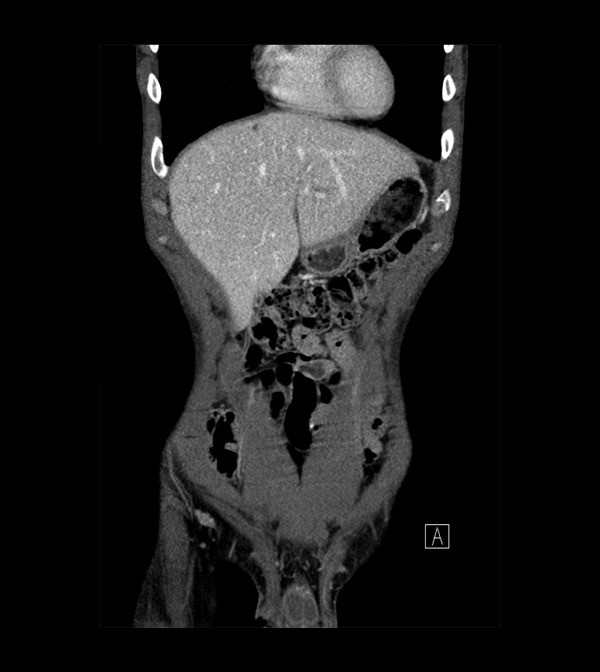

Body

Covers abdominal CT anatomy.